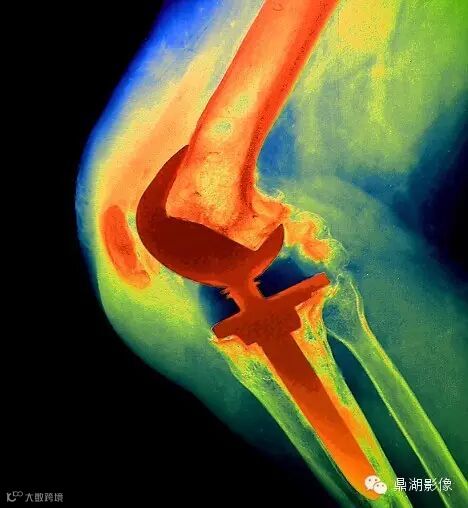

10膝关节炎

据一项英国学者对膝关节炎与高跟鞋的关系的研究发现,穿高跟鞋和赤足行走时髋、膝、踝关节的受力完全不同,经常穿高跟鞋会显着改变踝关节的正常功能,行走时人体必须由髋和膝关节代偿以保持步态稳定。长时间的紧张与压力可导致髌股关节腔内关节退行性改变,从而诱发膝关节炎。